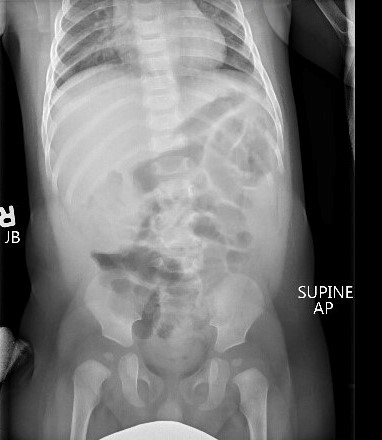

Evaluation may show a right upper quadrant mass or “sausage sign.” However, the absence of this on examination does not eliminate the need for further evaluation for intussusception, nor does the absence of pain at the time of presentation. Radiographs may show a paucity of bowel gas on the right, loss of the liver edge, and may even reveal the intussusception itself. (See Figure 3.) This is identified as a donut-like shape or “target sign” in the right upper quadrant, or as an intraluminal mass within the transverse colon, which may be identified by the “crescent sign” or “meniscus sign” of air within the lumen of the colon at the leading edge of the intussusceptum.28 The abdominal radiographs are abnormal in only 45% of cases of intussusception.30

Figure 3. Intussusception |

![]() |

The top image is a radiograph with intussusception visible along the edge of the liver. The bottom image is an ultrasound of intussusception. Images courtesy of Derya Caglar, MD. |

Ultrasound has become the primary and preferred method for diagnosing intussusception in the pediatric population. It has high sensitivity (98% to 100%) and specificity (88% to 100%) in the diagnosis of intussusception.33,34 (See Figure 3.) Air contrast enema reduction of intussusception has become standard, although it occasionally can be unsuccessful (less than 20% of primary attempts are unsuccessful at reduction) or cause perforation of the intestines (less than 1% incidence), necessitating surgical intervention.35 Unsuccessful first attempts at reduction can be repeated, with delays reported between 30 minutes to 24 hours between attempts. Success rates after delayed repeat attempts at reduction enemas are 50% to 82% successful.36 A meta-analysis comparing barium enema to air enema showed a higher success rate, lower perforation rate, decreased cost, and decreased fluoroscopy time for air enema.35